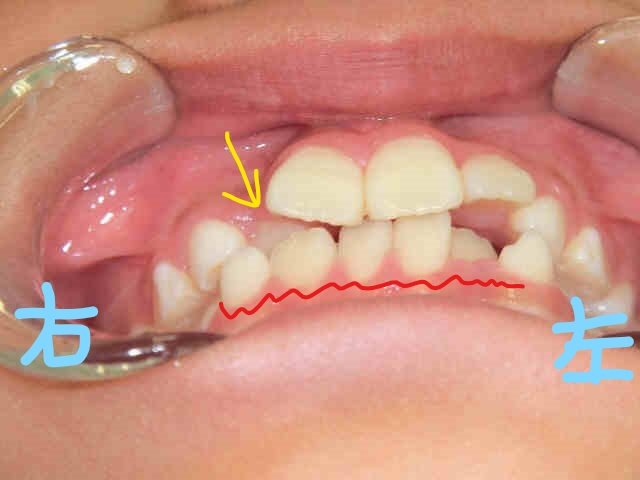

初診時の写真(左上:正面、右上:下から見上げた正面)では、右上前歯(黄色矢印)が内側に入り込み、下顎前歯(赤波線部)には叢生(歯列の重なり=ガタガタの歯並び)が見られました。

さらに上下顎の咬合面の写真からも、上顎前歯の内側移動と、下顎前歯の叢生が確認されます。

このまま成長を迎えた場合、叢生が進行し、犬歯が歯列外に萌出する「八重歯」の状態になる可能性がありました。